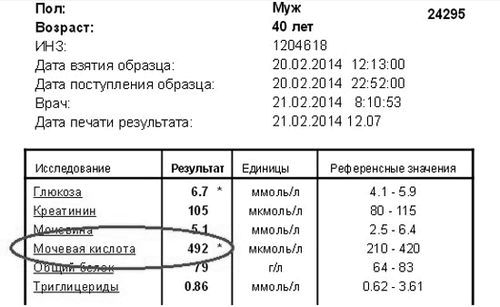

Діагноз уратурія ставиться за лабораторними даними, якщо виявлені солі сечової кислоти в крові та сечі. У нормі сечова кислота в них присутній у невеликій кількості, що не визначаються під час аналізу. Одноразове поява в сечі уратів вважається варіантом норми і зустрічається при важкій фізичній активності, білковій дієті, і інших станах. Повторне виявлення уратів в сечі і крові свідчить про наявність уратурія. Ступінь підвищення уратів позначається одним або декількома знаками «+». Одноразовий результат «+» або «++» - варіант норми, 3 або 4 (максимум) плюса, навіть одноразово - ознака уратурія.

Лабораторні симптоми, що дозволяють запідозрити сечокислий діатез у дорослих, - це висока або неодноразове підвищення кількості солей сечової кислоти в сечі, підвищення їх вмісту в крові. В біохімічному аналізі крові можуть бути присутніми маркери запалення і ферменти, які вказують на ушкодження м'язів. Також можуть бути ознаки інших захворювань, які провокують розвиток уратурія.

Розшифровка аналізу крові